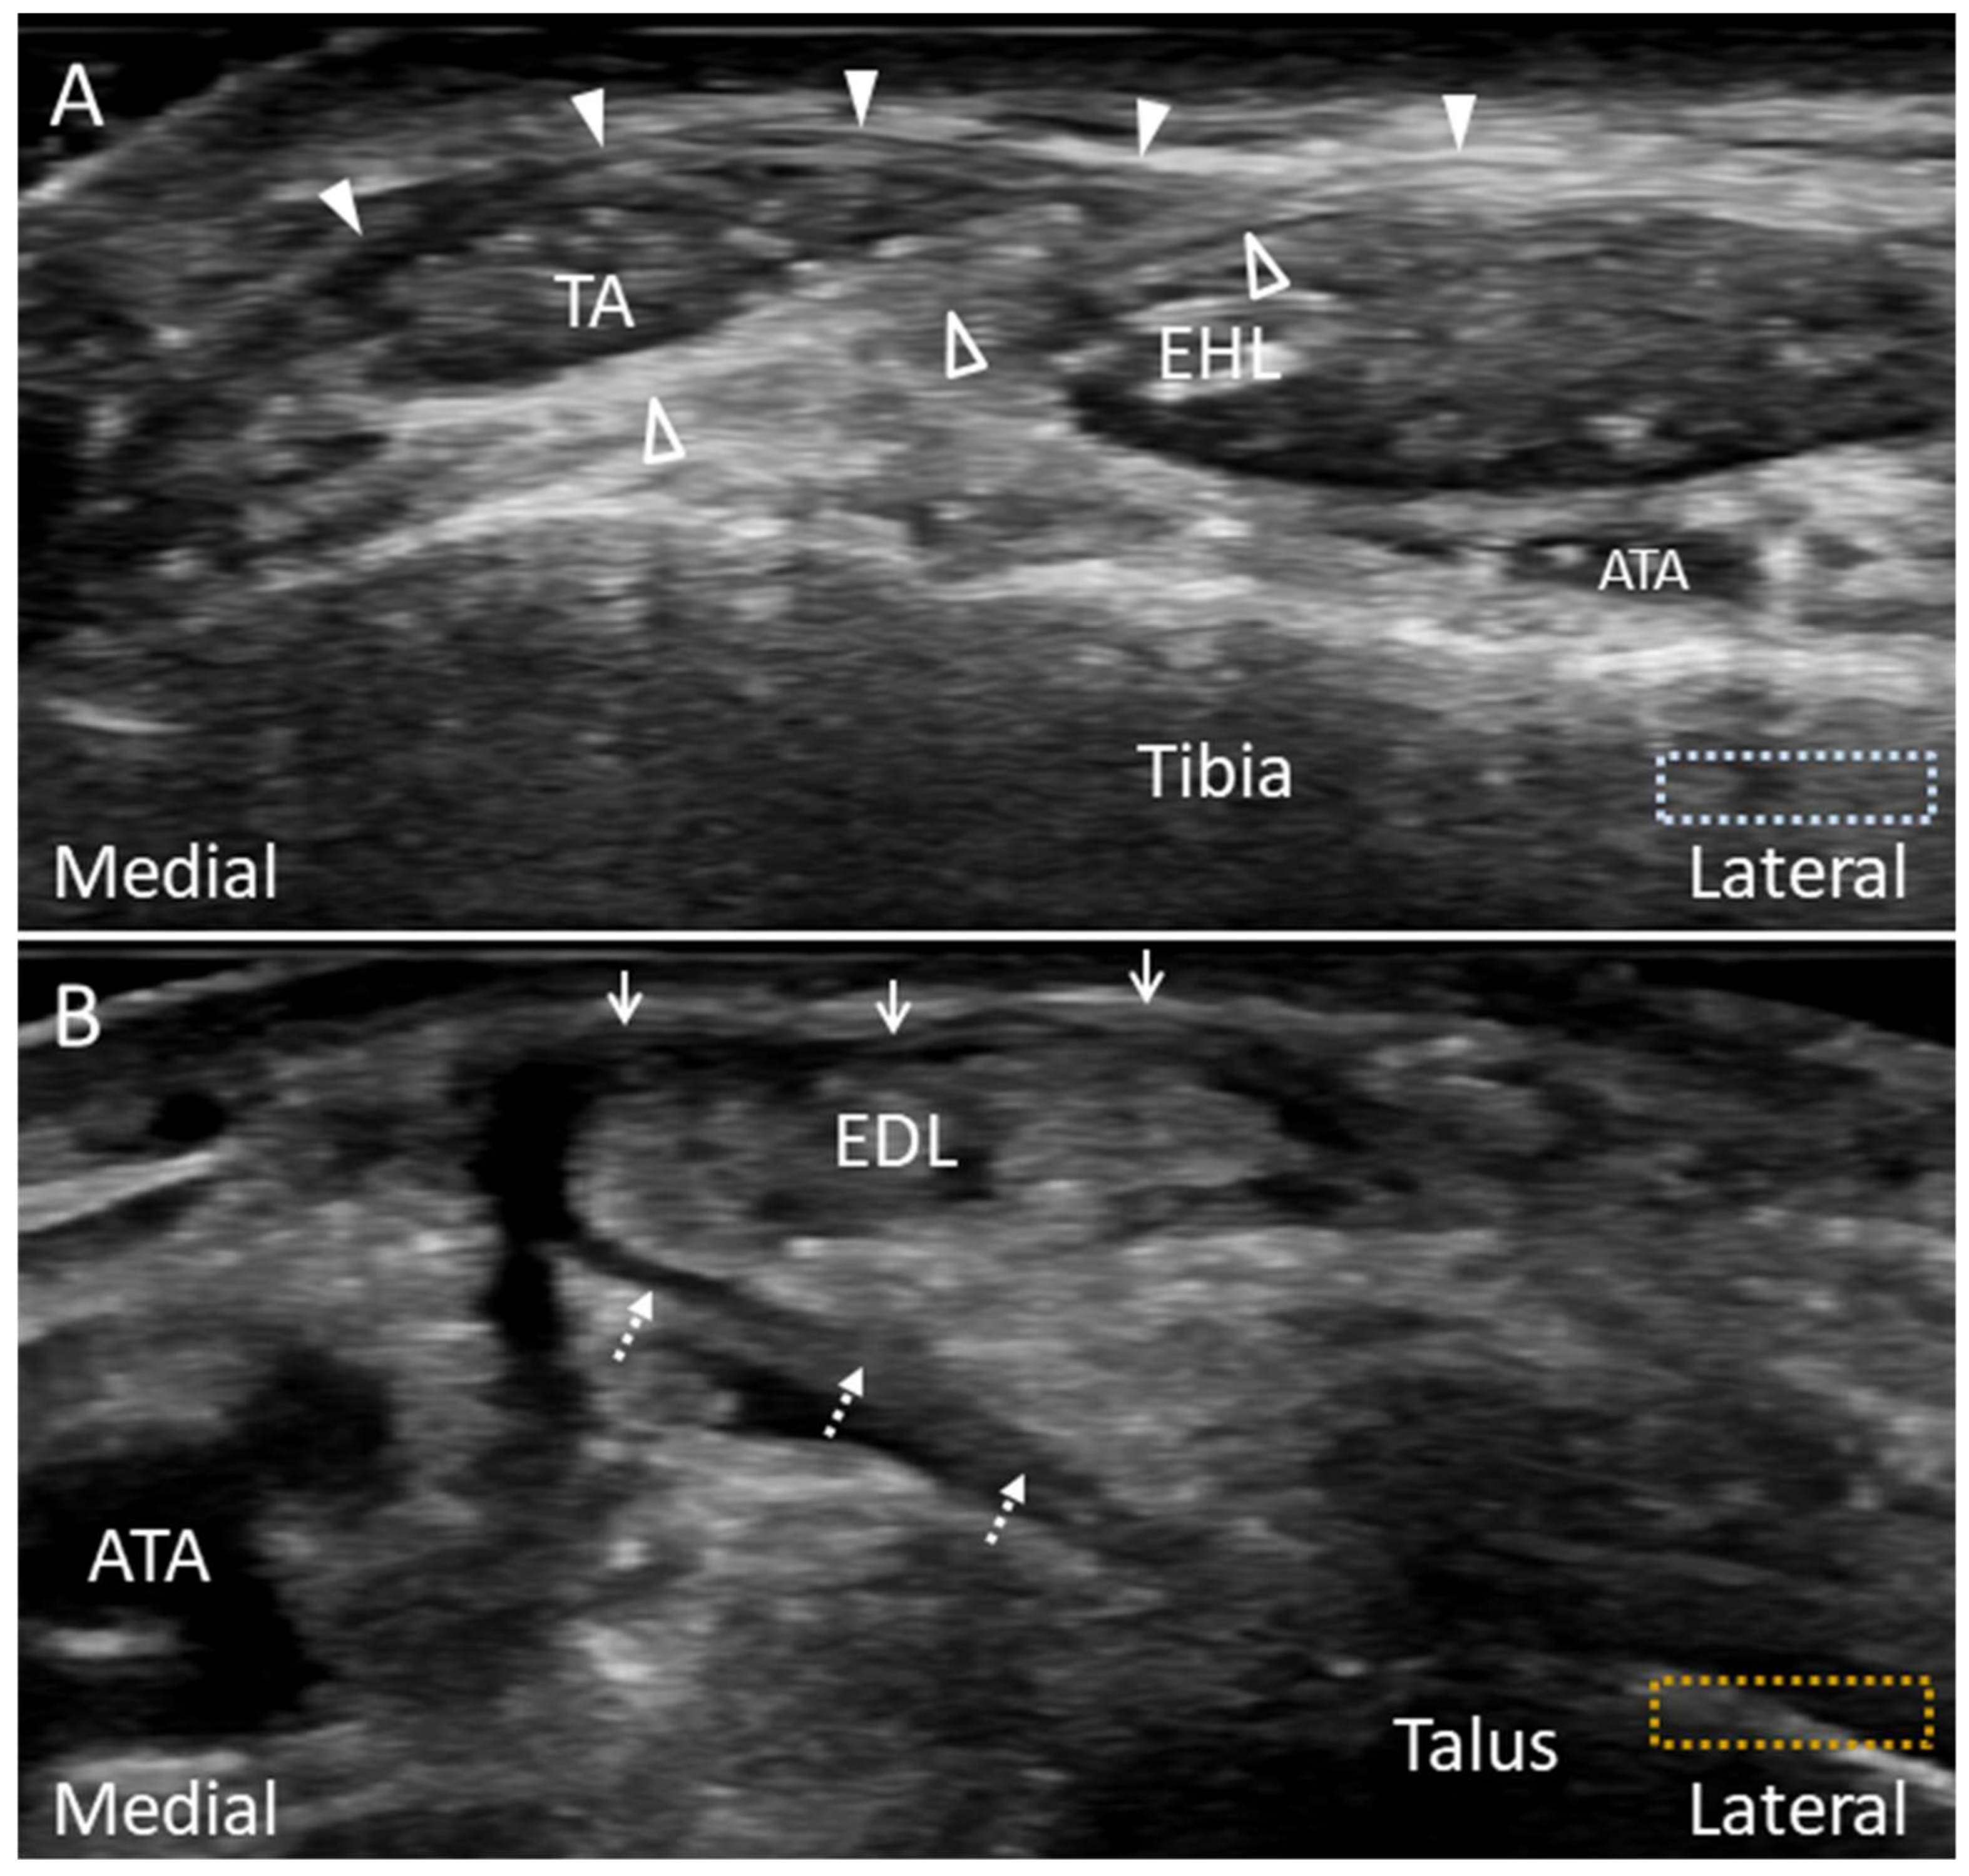

3.1. Anatomy

3.2. Scanning Technique

3.3. Clinical Relevance